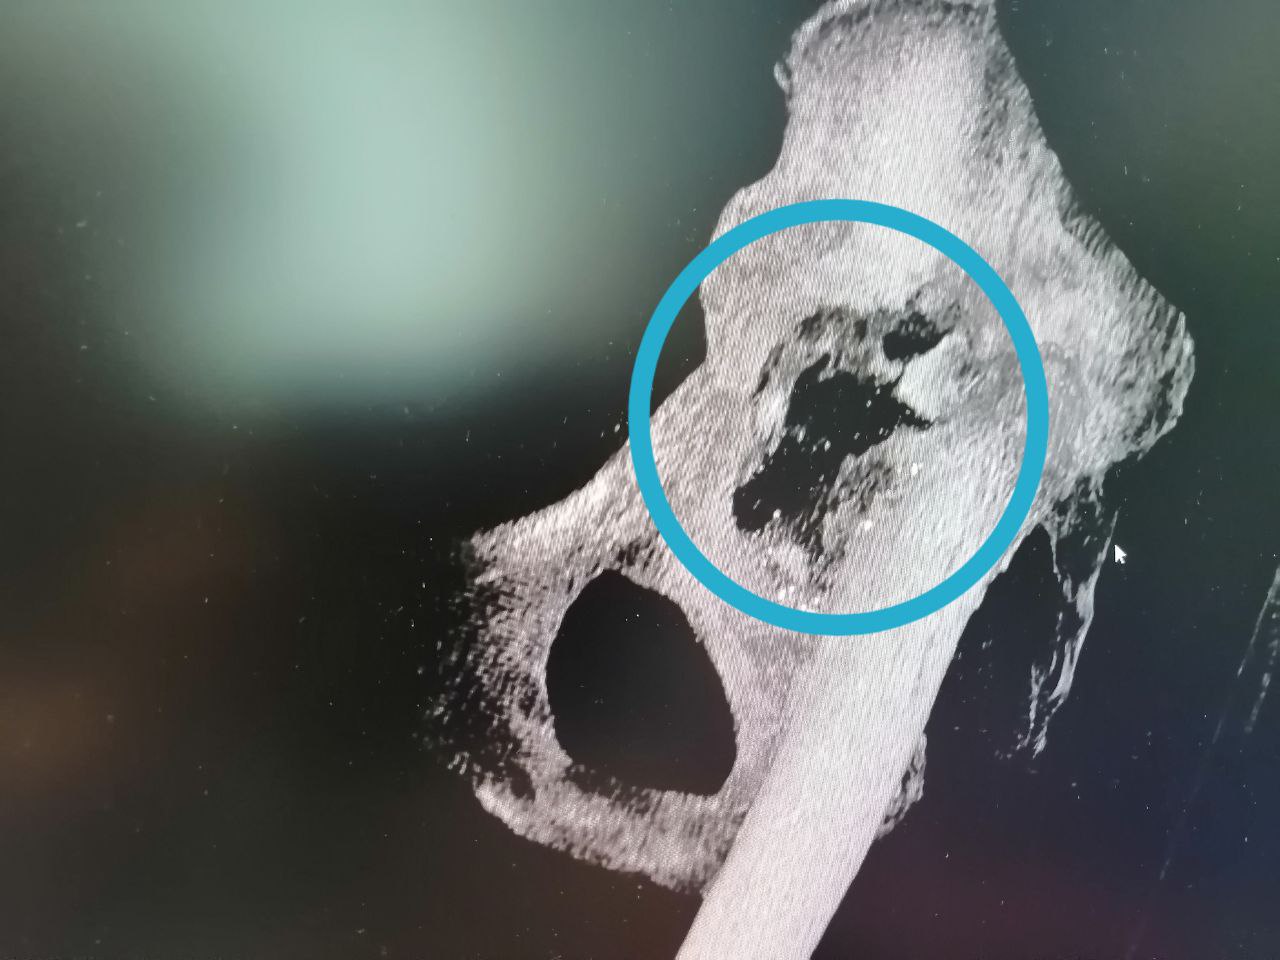

"Получили удовольствие от работы" - так оценивают первый опыт установки индивидуального имплантата травматологи-ортопеды Андрей Миронов и Евгений Бойко. Они совместно оперировали 70-летнюю пациентку с тяжелым дефектом тазовой кости. Стандартным эндопротезированием тазобедренного сустава проблема не решалась. Лизис превратил вертлужную впадину в решето, разрушив костные структуры на довольно большой площади (фото). Поэтому фиксировать эндопротез было просто не к чему.

По КТ-снимкам 3D-принтер напечатал точную копию поврежденной тазовой кости. Затем был смоделирован фрагмент для замещения дефекта. Его выполнили в двух вариантах: из полимерного материала – для пробной примерки и из титана – для окончательной установки. Во время хирургического вмешательства 3D-эндопротез идеально встал на своё место. Заместив разрушенный участок кости титановым «двойником», травматологи-ортопеды смогли приступить к следующему этапу лечения – эндопротезированию всего тазобедренного сустава. Через сутки пациентка уже вставала на ноги с помощью дополнительной опоры, а сегодня под контролем инструкторов-методистов ЛФК разрабатывает новый сустав при ходьбе.